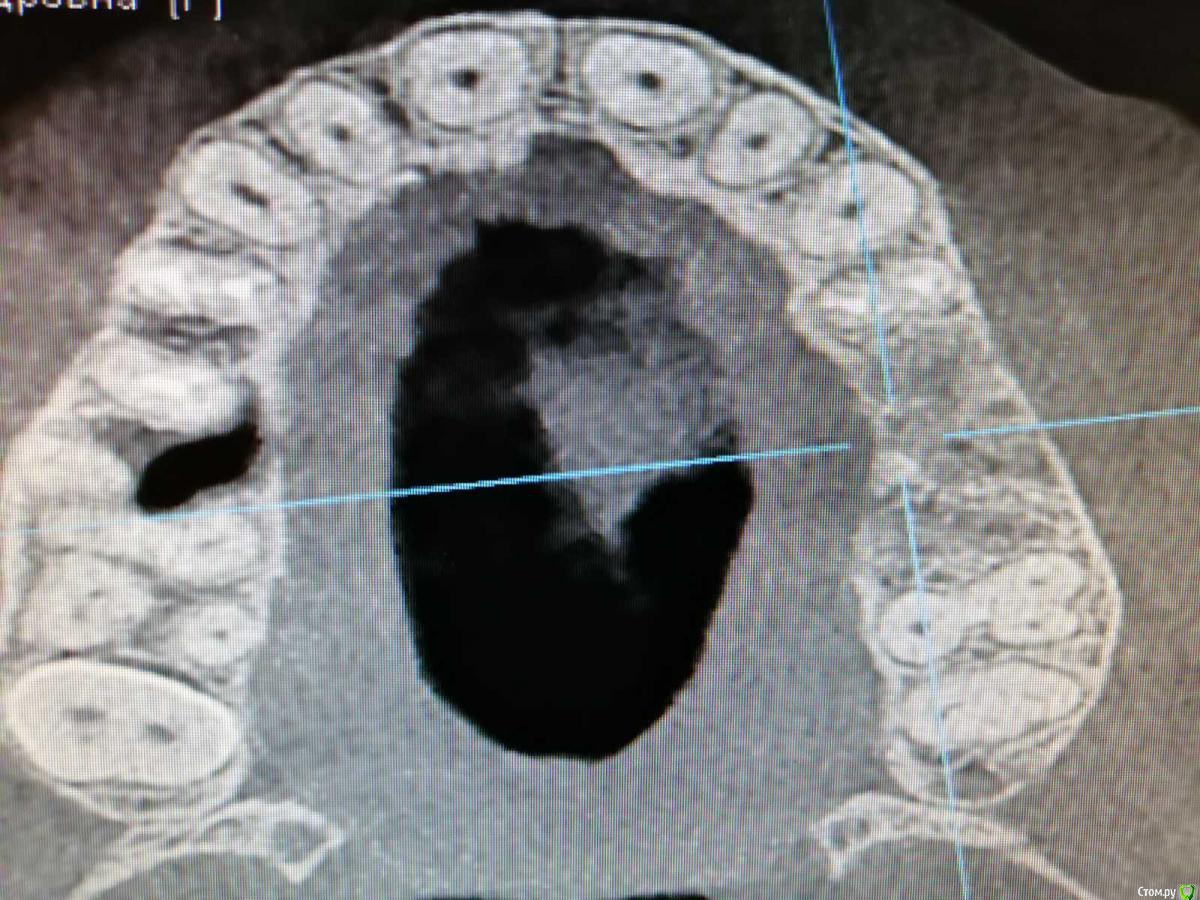

Добрый день. Встал вопрос об имплантации. Были удалены 5 и 6 зубы верхней челюсти. После удаления ничего не беспокоило. Все затянулось десной. через 3 мес. новое КТ. На снимке видно твердое тело в гайморовой пазухе. Врач(не тот который удалял) сказала, что мне надо обращаться к лору. Посоветуйте что делать? Меня не беспокоит челюсть. Дышу я хорошо.

Никаких ощущений нет плохих. Можно будет обойтись без госпитализации? Первый снимок до удаления и два спустя 3 мес после удаления.